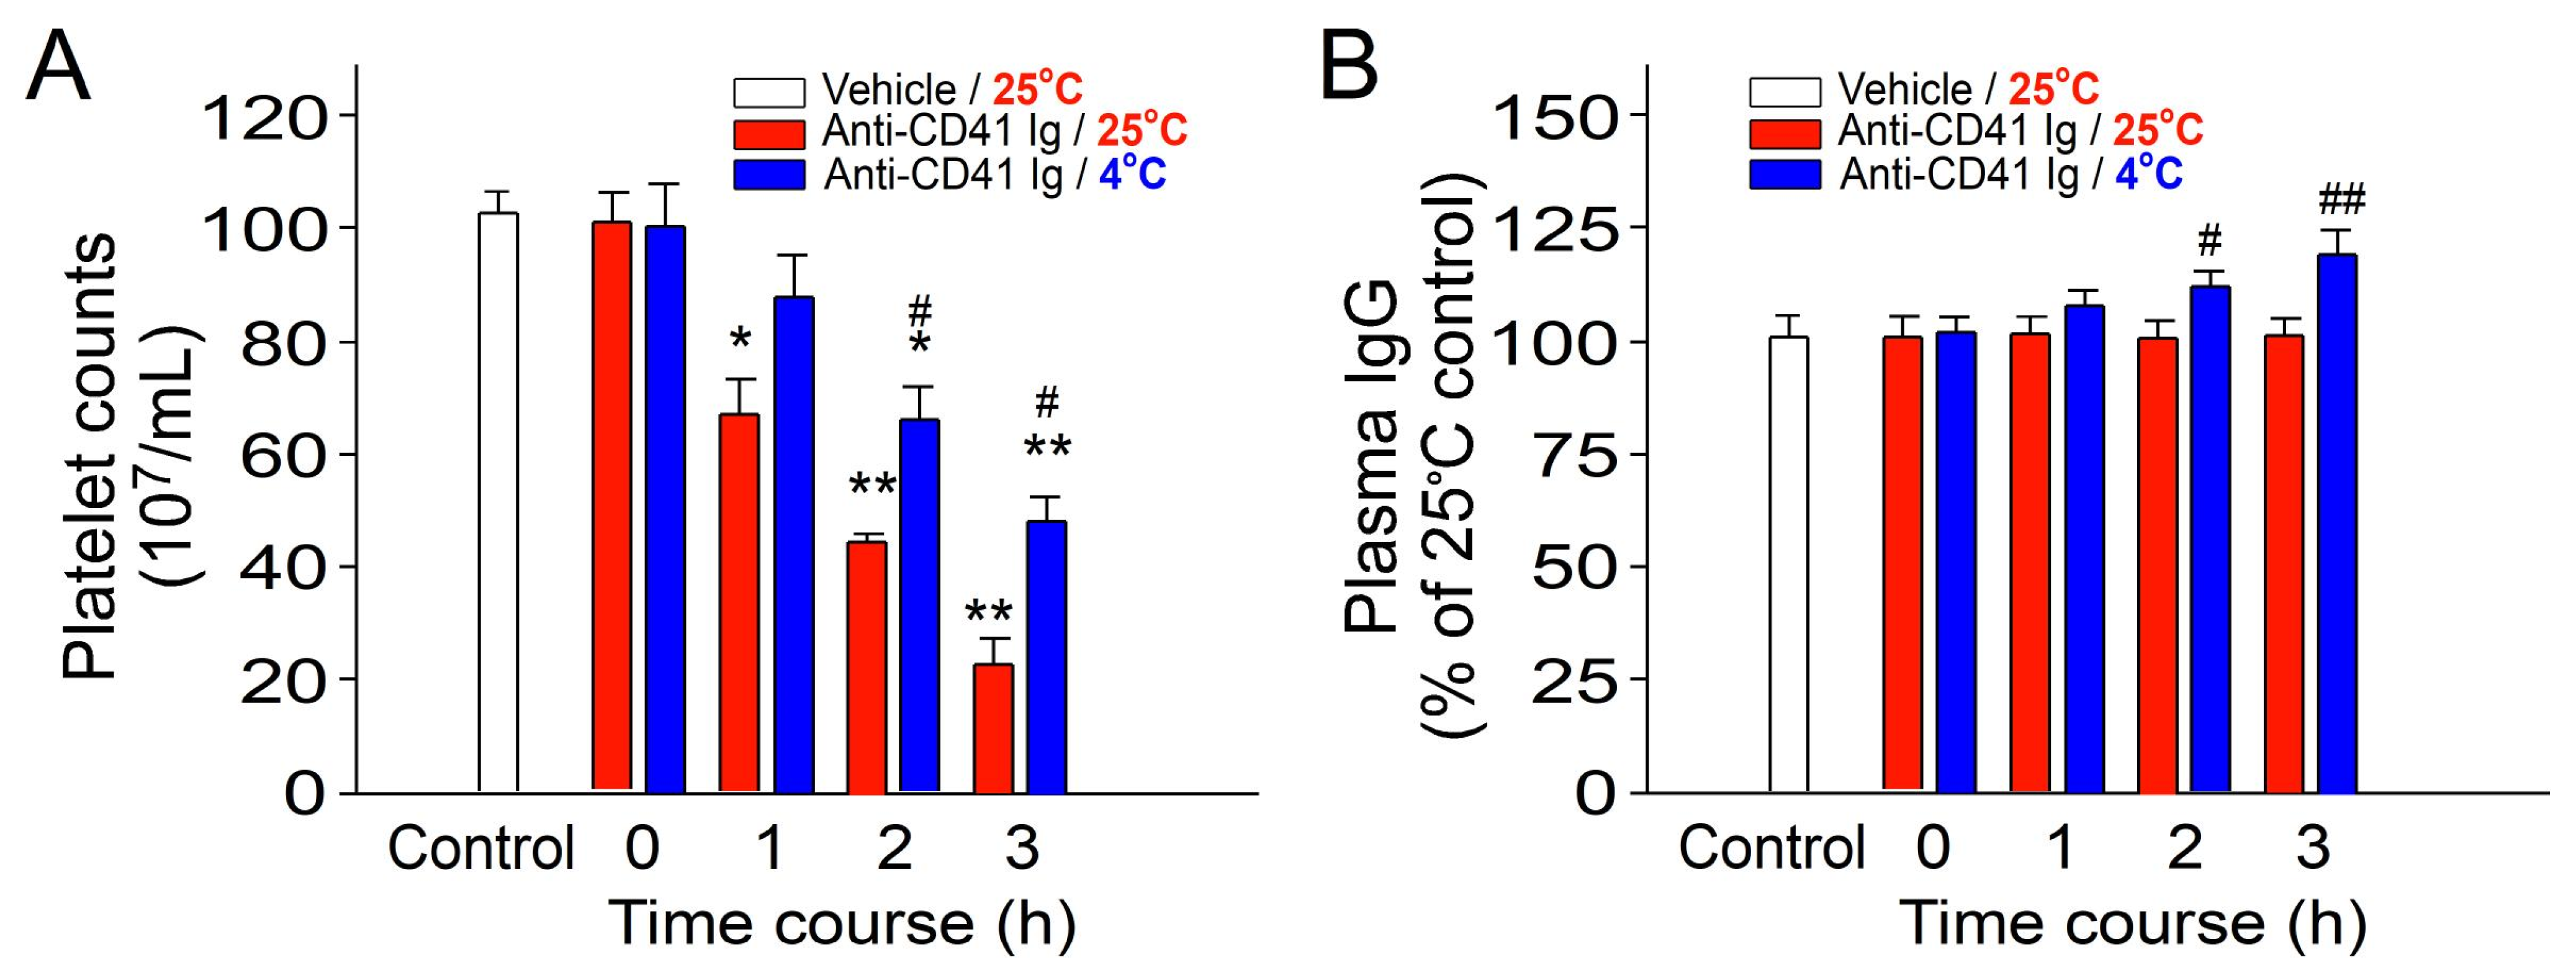

2.1. Cold-Induced Immunosuppression Revealed by Ameliorated Immune Thrombocytopenia and Increased Circulating IgG Levels in Mice

4.2. Measurements of Plasma IgG Levels in the Cold Exposure Mouse Model

4.3. Induction of Experimental Immune Thrombocytopenia (ITP) in the Cold Exposure Mouse Model